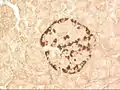

A pancreatic islet, stained.

A pancreatic islet, stained. A pancreatic islet, showing alpha cells

A pancreatic islet, showing alpha cells A pancreatic islet, showing beta cells.

A pancreatic islet, showing beta cells.